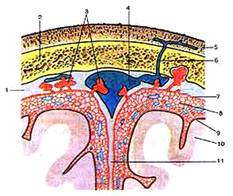

Строение сердца. Общие сведения

Сердце (cor) у человека четырехкамерное. В

Сердце окружено околосердечной сумкой –

перикардом (pericardium), отделяющей его от других органов. Стенку сердца

образуют три слоя: наружный – эпикард (epicardium – 13), средний – миокард

(myocardium – 11), внутренний – эндокард (endocardium – 12). Эпикард

представляет собой часть серозной оболочки, состоящей из двух листов: наружного

– перикарда и внутреннего – непосредственно эпикарда. Миокард – мышечная

оболочка сердца, в предсердиях она тонкая (около 2 см.), а в желудочках достигает

15 см. По своему строению миокард – поперечно-полосатая мышца, синцитий.

Эндокард образован эндотелием и выстилает все

полости сердца.

Строение правого предсердия и желудочка

верхняя полая вена (1), нижняя полая вена (14) и венечный синус (13). Верхняя

часть правого предсердия образована правым ушком сердца (5). Правое предсердие

сообщается с правым желудочком при помощи предсердно-желудочкового отверстия.

Правый желудочек имеет форму треугольной

пирамиды, с верхушкой обращенной вниз и располагается справа и спереди от

левого желудочка. От левого желудочка отделяется при помощи межжелудочковой

перегородки. Вверху в стенке желудочка есть два отверстия: сзади – правое

предсердно-желудочковое, а спереди – отверстие легочного ствола.

Предсердно-желудочковое отверстие закрывается при помощи трехстворчатого

клапана (8). Внутри правого желудочка находятся трабекулы и сосочковые мышцы,

от которых к створкам клапана идут сухожильные хорды. Из правого желудочка

начинается легочной ствол (6). Между правым желудочком и легочным стволом

находится полулунный клапан легочного ствола.

Строение левого предсердия и желудочка

Левый желудочек (16) конусовидный, его основание

обращено кверху. В переднем верхнем отделе желудочек сообщается с аортой. У

места выхода аорты из левого желудочка имеется клапан аорты, который состоит из

правой, левой и задней полулунных заслонок. В предсердно-желудочковом отверстии

располагается двухстворчатый клапан (митральный – 7).

На внутренней поверхности левого желудочка

находятся мясистые трабекулы (10) и две сосочковые мышцы (9), от которых идут

сухожильные хорды (8), прикрепляющиеся к свободным краям створок митрального

клапана.

Толщина стенок левого предсердия около 2 мм, а

желудочка – до 15 мм. Верхушку сердца полностью выполняет левый желудочек.